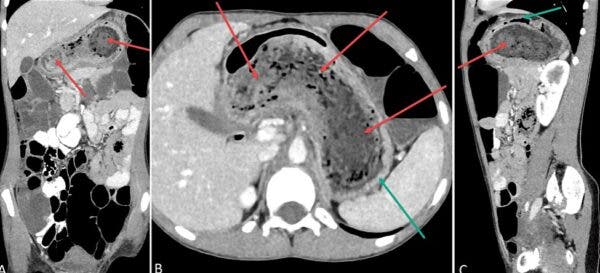

Fata avea nevoie urgent de operație. Medicii i-au găsit în stomac mult păr, astfel că chirurgii unui spital din Cehia i-au îndepărtat un ghemotoc uriaş de mărimea unui pahar de jumătate de litru, prin laparoscopie, a scris Pro TV. Smocul, în formă de cilindru, cu o lungime de 20 de centimetri şi un diametru de 8 centimetri, era mult prea mare pentru a fi îndepărtat pe gură.